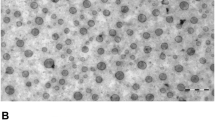

3.4 The cell morphologies and ultrastructural changes induced by SBI-115 in vitro

For further research, we treated cells with SBI-115 or DMSO at an initial density of 3 × 104 cells/ml for 48 h in complete culture medium, then the clear visualization of cell morphologies and ultrastructural changes were observed under inverted microscope and transmission electron microscope, respectively. In the control group, human PANC-1 and BXPC3 cells exhibited full body, clear border and close arrangement. Meanwhile, PANC-1 and BXPC3 cells treated with SBI-115 showed unregulated-shaped body and more visible vacuoles (Fig. 4A). Furthermore, the transmission electron microscopy was used to determine the ultrastructural changes in SBI-115-treated cells. It was shown that the mitochondria in SBI-115-treated cells exhibited decreased mitochondrial cristae, swollen-shaped body and ruptured mitochondrial membranes while the mitochondria in DMSO control groups were linear with an integral structure (Fig. 4B).

The cell morphologies and ultrastructural changes induced by SBI-115 in vitro. A The cellular morphologies of PANC-1 and BXPC3 cells were observed by using the light inverted microscope (100 ×); B The ultrastructural changes in PANC-1 and BXPC3 cells were observed by transmission electron microscope (1 μm). The red arrows indicated the mitochondria

For further study, the cell morphologies and ultrastructural changes induced by SBI-115 in pancreatic cancer cells were further examined. Morphologically, PANC-1 and BXPC3 cells treated with SBI-115 exhibited unregulated-shaped bodies and more visible vacuoles, and the transmission electron microscopy showed the mitochondria in SBI-115-treated cells exhibited decreased mitochondrial cristae, swollen-shaped body and ruptured mitochondrial membranes. Mitochondria are important organelles for cellular physiology and homeostasis in most eukaryotic organisms, and bile acids could directly act on the mitochondria [39]. TGR5 ablation did influence the mitochondrial biogenetic pathway [40]. Our results demonstrated that antagonism of TGR5 would lead to the abnormal structure of mitochondria in pancreatic cancer cells, but further verification was also still needed.